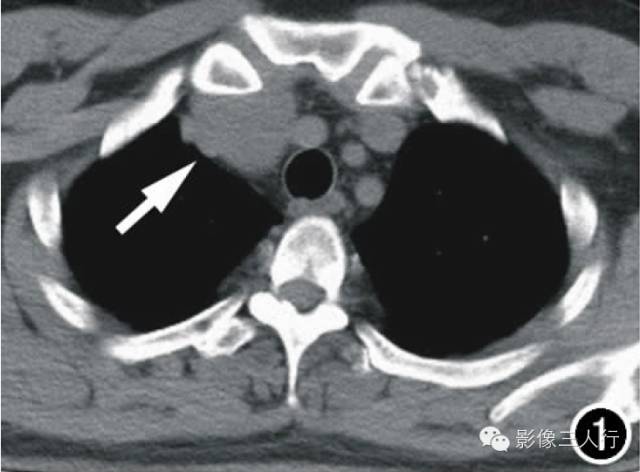

张力性纵隔气肿影像表现及严重度分级